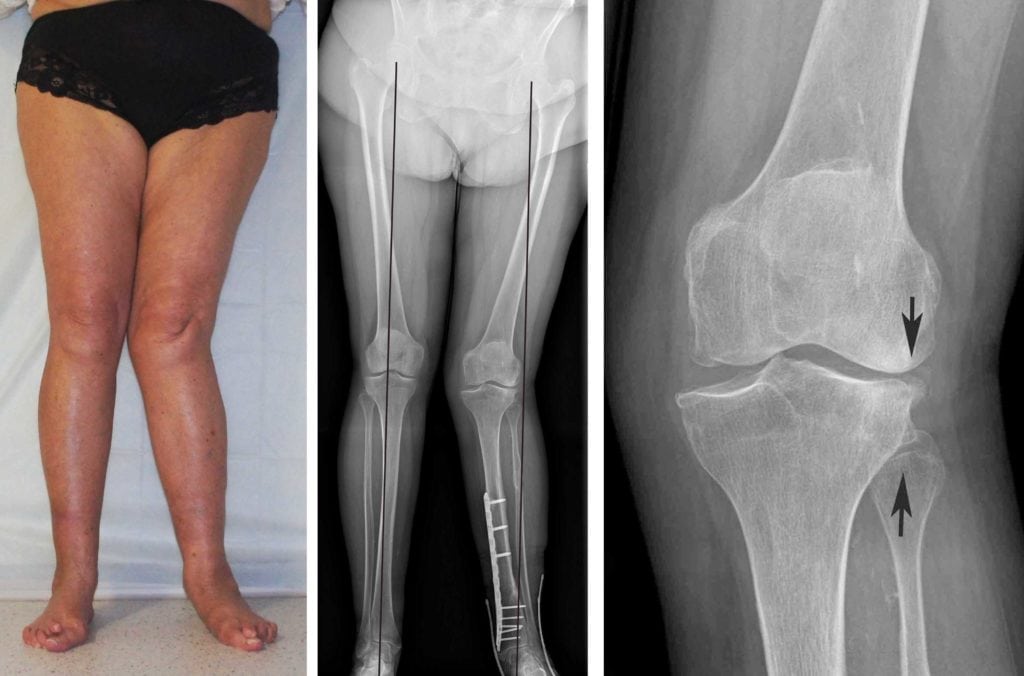

Вальгусная деформация коленных суставов — аномалия развития наследственного характера. При внешнем осмотре взрослого или ребенка ортопедом наблюдается Х-образное искривление ног. Одним из симптомов патологии становится боль в коленях, усиливающаяся после длительной ходьбы или подъема тяжестей. На рентгенографических снимках хорошо визуализировано нарушение процессов окостенения, а наружный мыщелок бедра выглядит скошенным.

Вальгусная деформация у взрослых часто сопровождается коксартрозом или гонартрозом, поэтому проводится дополнительное рентгенологическое обследование тазобедренного сустава. В терапии заболевания 1-2 степеней используются консервативные методы — массаж, физиопроцедуры, лечебная гимнастика, ношение ортопедической обуви. Пациентам с тяжелыми аномалиями показано хирургическое вмешательство, обычно остеотомия бедренной кости. Операции проводятся и в пожилом возрасте, поскольку являются единственным методом предотвращения развития артроза.

Ортопед выставляет диагноз уже при внешнем осмотре маленького или взрослого пациента по Х-образной форме ног. Чтобы выбрать оптимальный метод лечения, устанавливается степень вальгусной деформации. Для начальной степени характерно отклонение голени в сторону не более чем на 15°. При вальгусе второй степени — 15°-20°. Искривление третьей, самой высокой степени тяжести, сопровождается отклонением голени наружу на 20° и более.

Хирургическое вмешательство практикуется при неэффективности консервативной терапии и диагностировании вальгусной деформации коленей у пациентов с остеоартрозом. Во время проведения операции часть берцовой кости удаляется, а затем происходит ее дальнейшее сращение. Хирургическое вмешательство при вальгусе у детей и подростков заключается сразу в придании ноге анатомического положения. Вальгусная деформация относится к прогрессирующим патологиям, поэтому результативность лечения зависит от своевременного обращения к врачу.